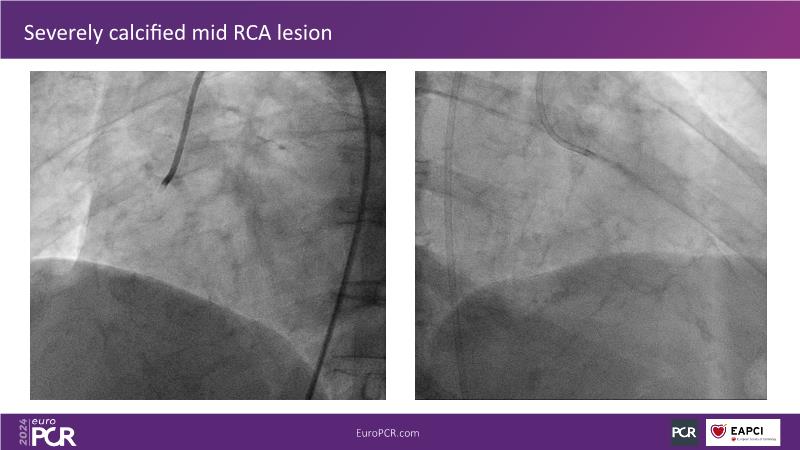

Follow this session to learn about the novel HC-IVL system, its application for moderate to severe calcified lesions, and procedural tips. The LithiX Hertz Contact IVL addresses unmet needs in coronary artery calcification by offering a simplified workflow with fewer devices and effective treatment for difficult lesions. Its novel design ensures safety and efficacy, with the PINNACLE I study's primary outcomes expected to confirm its effectiveness.

- To understand types of moderate to severe calcified lesions that can be successfully treated with HC-IVL